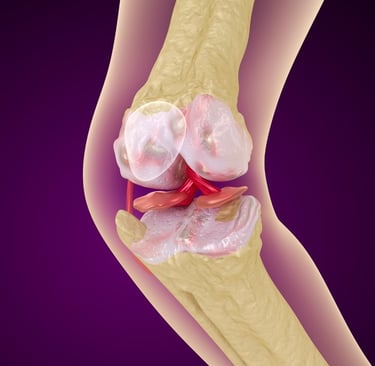

Diz kireçlenmesi, tıbbi adıyla osteoartrit, özellikle 50 yaş üstü bireylerde hareket kısıtlılığının ve kronik ağrının en büyük nedenlerinden biridir. Dizdeki kıkırdak dokusunun zamanla aşınmasıyla ortaya çıkan bu durum, "yaşlılık hastalığı" olarak bilinse de günümüzde yanlış beslenme ve hareketsizlik nedeniyle daha erken yaşlarda da görülmektedir.

Peki, her diz kireçlenmesi mutlaka protez ameliyatı ile mi sonuçlanmalıdır? Hayır. Günümüzde cerrahiye gerek kalmadan diz sağlığını koruyan ve ağrıları dindiren pek çok yenilikçi yöntem mevcuttur.